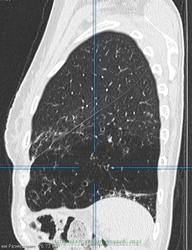

Женщина 50 лет, поступила в стационар с жалобами на субфебрилитет, постоянно рецидивирующие бронхит и пневмонию на протяжении 2 лет. Выполнена ФЛГ - подозрение на сегментарную инфильтрацию в верхней доле правого легкого, повышена воздушность нижней доли левого легкого.Выполнена КТ - с чем бы Вы дифференцировали процесс, коллеги?

Выложил ключевые изображения, толщиной 5 мм, легочное окно, Kernel 90. Если требуется DICOM - выложу позже

вообще то это зона фиброателектаза с тракционными бронхоэктазами(слева ),справа в верхней доле многогоузловое с утолщенным интерлобулярным интерстицием переходящим на междолевую плевру (локальное утолщение ее ),признаков тракции ее не обнаружено,на фронталах по периферии крупного узла утолщенный интралобулярный интерстиций(локального лимфостаза не обнаружено )-вообщем все старое .хотелось бы на все в медиастинальном окне посмотреть ,а так специфику с неспицификой

Там и циллиндрические бронхоэктазы, и центрилобулярная эмфизема. В обоих легких, больше в левом. Бронхиолы сильно расширены, практически до субплевральных отделов, причем бронхоэктазы есть не только в нижних отделах, но и в верхних. На последней 3Д реконструкции неплохо отображено бронхиальное дерево. оно патологическое.